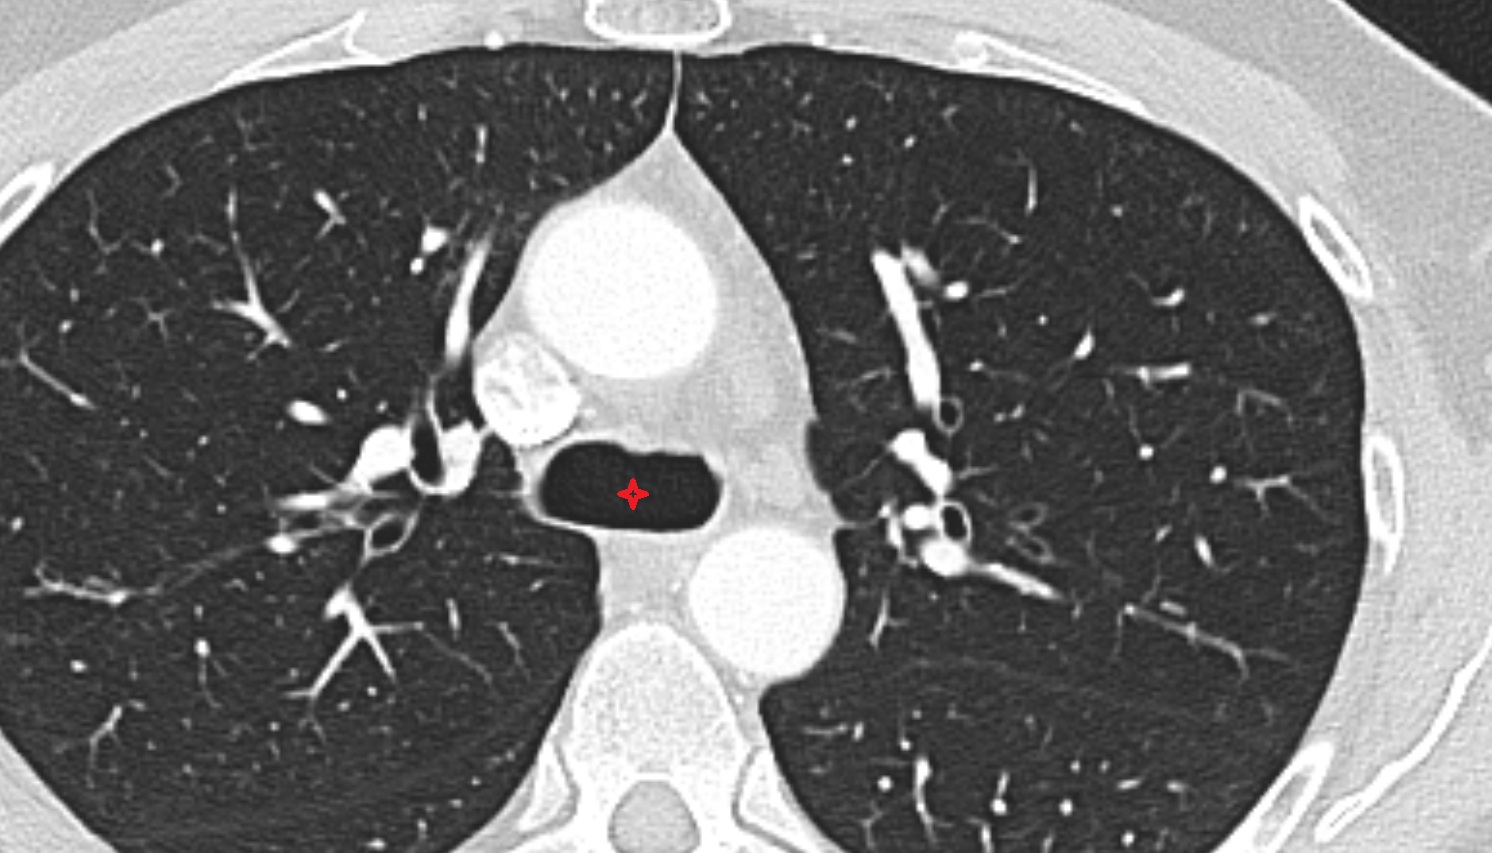

- Trachea

- Right main bronchus

- Left main bronchus

- Carina of trachea

- Tracheal bifurcation

- Subcarinal lymph nodes

- Superior tracheobronchial lymph nodes